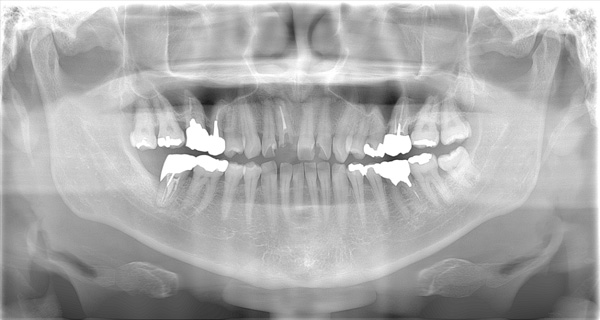

| 年代・性別 | 50代 男性 |

|---|---|

| 主訴 | 右上下の歯が痛い |

| 治療期間 | 約12ヶ月 |

| 費用 | 2,500,000円 |

| 治療内容 | インプラント、骨造成、結合組織移植、セラミック修復 |

| 治療に伴うリスク | インプラント周囲炎 セラミックの破折、脱離 |

*キャンセルポリシーをご一読のうえご予約ください